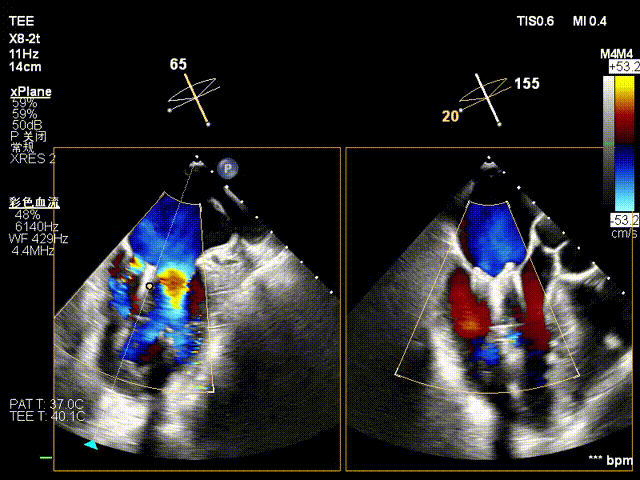

在全麻下,于心尖入路完成ValveClamp®装置植入。术中多学科团队密切配合,超声全程实时指导操作。最终,于2偏3区成功植入一枚Ⅲf夹子,一次夹合完成。前叶夹合量12mm,后叶夹合量10mm,反流降至1+,导管操作时间30分钟。术后平均跨瓣压差3mmHg。

术前反流 术后反流